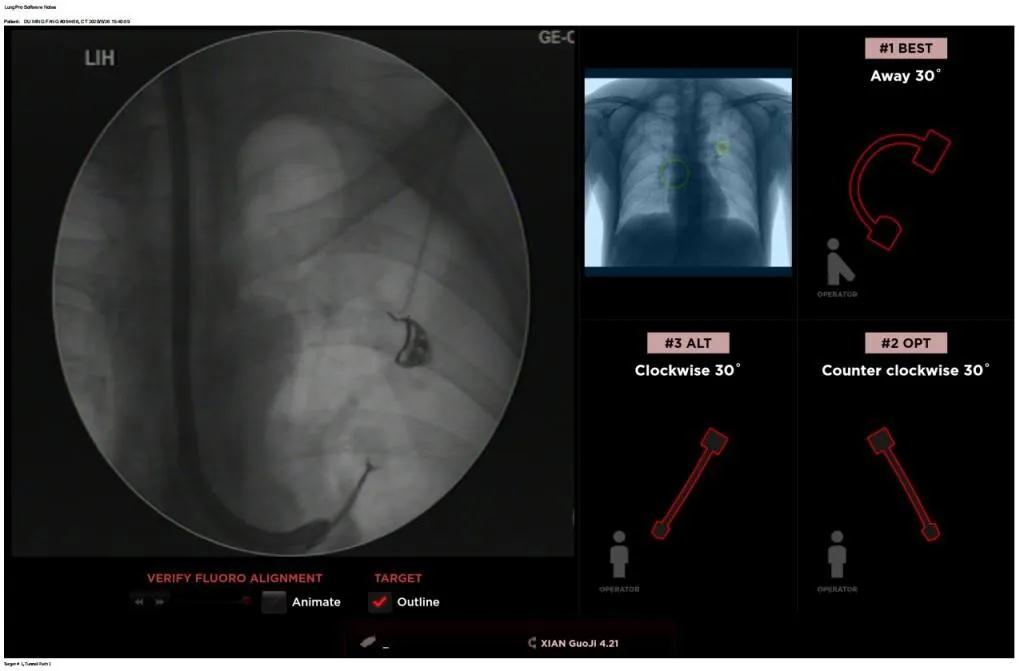

近日,西安國際醫(yī)學中心醫(yī)院胸科醫(yī)院歐陽海峰副院長完成西北地區(qū)首例LungPro全肺導航系統(tǒng)引導下經(jīng)支氣管鏡跨肺實質(zhì)肺外周結(jié)節(jié)活檢術(shù)。

患者是一位59歲的男性,入院診斷左固有上葉前段肺小結(jié)節(jié),大小1.5cm*1.5cm。因為病灶與支氣管不相通,無法開展經(jīng)支氣管自然腔道的活檢,而且病變距離胸壁較遠、肋骨阻隔進針線路、病灶周圍有血管包繞,如果進行CT引導下經(jīng)皮肺穿刺活檢,則存在較大的氣胸、出血等并發(fā)癥的風險。

經(jīng)過充分的討論后,歐陽海峰副院長決定為患者實施LungPro全肺導航系統(tǒng)引導的經(jīng)支氣管跨肺實質(zhì)肺外周結(jié)節(jié)活檢術(shù)。Broncus導航系統(tǒng)LungPro具有全球領先獨創(chuàng)的BTPNA技術(shù)(支氣管鏡下跨結(jié)節(jié)抵達術(shù)),可以實現(xiàn)對氣道外周孤立性肺小結(jié)節(jié)的精準定位,建立直接通往氣道外病變部位的通道,以實現(xiàn)全肺的診斷及后續(xù)治療。這項技術(shù)不僅彌補了現(xiàn)有支氣管鏡技術(shù)由于受限于病變部位是否有氣道可通向以及無法準確定位病變部位而造成的較低診斷率,同時還彌補了CT引導下經(jīng)胸穿刺(TTNA)無法適用于某些特定部位如中央及肩胛骨等結(jié)節(jié)的問題,并且還避免了經(jīng)胸穿刺給患者帶來氣胸、出血的高風險,可有效提高肺部結(jié)節(jié)及早期肺癌診斷陽性率,亦可用于早期肺癌的射頻消融或微波治療,具有微創(chuàng)、安全、同期雙肺診療等優(yōu)勢。

BTPNA技術(shù)整合了虛擬導航支氣管鏡VBN、氣道內(nèi)超聲rEBUS、TBNA、高壓球囊擴張、X線輔助等多項三、四級呼吸內(nèi)鏡技術(shù)。歐陽海峰副院長有3000 TBNA、1000 rEBUS、500 VBN、800 球囊擴張方面的技術(shù)積累,10年來個人每年完成三、四級呼吸內(nèi)鏡手術(shù)1200余例,這有效保障了BTPNA技術(shù)的順利開展。

團隊術(shù)前進行了精心的準備,通過高分辨率CT建立了導航路徑,在麻醉科手術(shù)室的配合下,借助LungPro引導順利的確定了病灶部位、建立隧道并實施活檢,術(shù)后患者恢復順利出院。